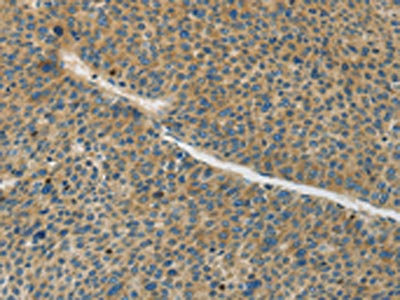

The image on the left is immunohistochemistry of paraffin-embedded Human liver cancer tissue using CSB-PA078531(GJC1 Antibody) at dilution 1/50, on the right is treated with synthetic peptide. (Original magnification: ×200)